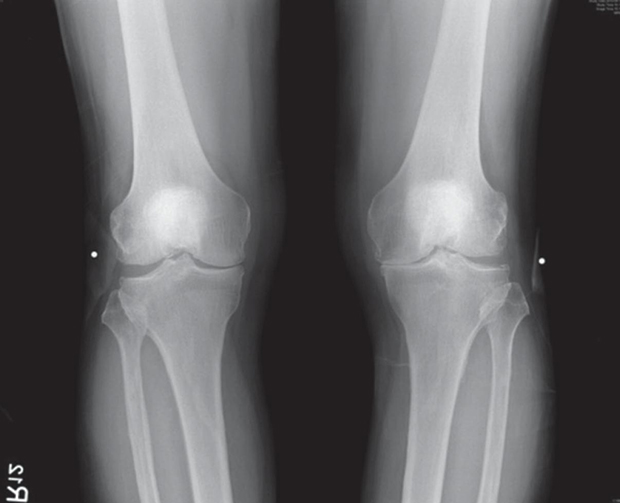

去年,接受治療前的X光片,兩膝內側關節間隙幾乎消失,右膝第三期,左膝已是第四期。

圖/手術前。